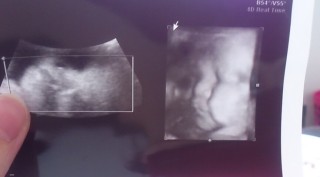

妊娠36週5日 36w5d の超音波 エコー 写真